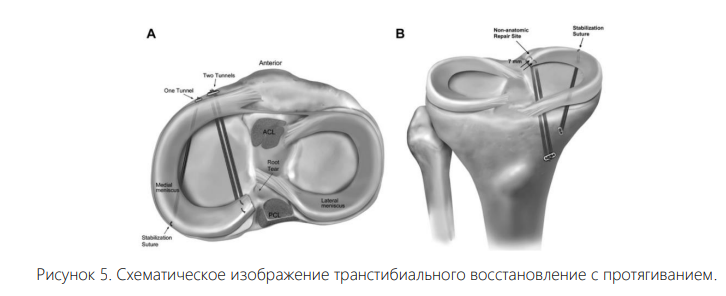

Недавнее сравнительное исследование пациентов, прошедших ЧMЭ, и пациентов, прошедших нехирургическое лечение, показало плохие клинические результаты и прогрессирование до ТЭКС в 54 % случаев в среднем через 54,3 месяца у тех, кто прошел ЧMЭ. Женский пол, повышенный ИМТ и выпячивание мениска были связаны с худшими результатами [1]. Методы лечения. Лечения РКМ в основном выполняется путем прямой фиксации с помощью шовных анкеров или с помощью швов, продетых через транстибиальный туннель. При прямом сравнении Ким и его коллеги обнаружили, что эти два метода дают одинаковые результаты. Каждая конструкция продемонстрировала сходное уменьшение выпячивания мениска, разрывов медиального корня и частоты полного заживления [7]. Хотя реконструкция показала превосходные результаты по сравнению с менискэктомией и нехирургическим лечением, погрешность в достижении функционально адекватной реконструкции, по-видимому, невелика. Старке и соавторы сообщили, что всего 3 мм смещения при размещении реконструкции значительно снижают биомеханические способности мениска [7]. Конструкции с анкировыми швами позволяют восстанавливать корень без создания туннелей в кости большеберцовой кости, что позволяет использовать их у пациентов с сопутствующей многосвязочной патологией или незрелостью скелета. Эта полностью артроскопическая техника была впервые описана Энгелсон [9], а последующие модификации описаны Ли эт ал. [9]. После первоначальной вертикальной фиксации шва на задней и передней трети мениска создается заднемедиальный портал. Постеромедиальный портал находится рядом с нервно-сосудистым пучком и требует использования специальных артроскопических инструментов. Хотя эта техника восстановления имеет и другие преимущества, такие как размещение анкеров ближе к естественному корню и минимальное повреждение кости большеберцовой кости, она технически сложна и требует большой осторожности, чтобы минимизировать повреждение хрящевой ткани и близлежащего нервно-сосудистого пучка. Транстибиальное восстановление с протягиванием.

При транстибиальном ремонтировании с протягиванием используется трансоссальный туннель для редукции корня мениска к тибиальному плато с помощью швов, закрепленных на передней кортикальной кости большеберцовой кости. Хотя эта техника может мешать сопутствующим процедурам, таким как высокая остеотомия большеберцовой кости, она представляет собой прагматичный подход, который менее сложен с технической точки зрения, исключает необходимость создания заднего портала, прилегающего к критическим нервно-сосудистым структурам, и не требует специальных устройств для прохождения швов [18].

Схематическое изображение транстибиального восстановление с протягиванием.

Техника транстибиального протягивания является надежным, безопасным и прагматичным методом восстановления корня мениска с доказанной эффективностью. Централизация мениска — это новая стратегия, применяемая перед восстановлением корня с целью уменьшения выпячивания путем фиксации или «централизации» средней части мениска к суставной поверхности большеберцовой кости.